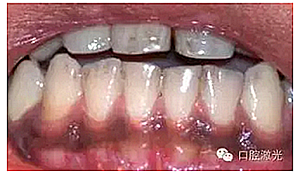

術(shù)后即刻

患者術(shù)后無明顯疼痛不適,沒有出現(xiàn)大量出血、感染或結(jié)痂現(xiàn)象。整個(gè)恢復(fù)過程較為順利?;颊呓邮芏雀?,治療效果明顯。